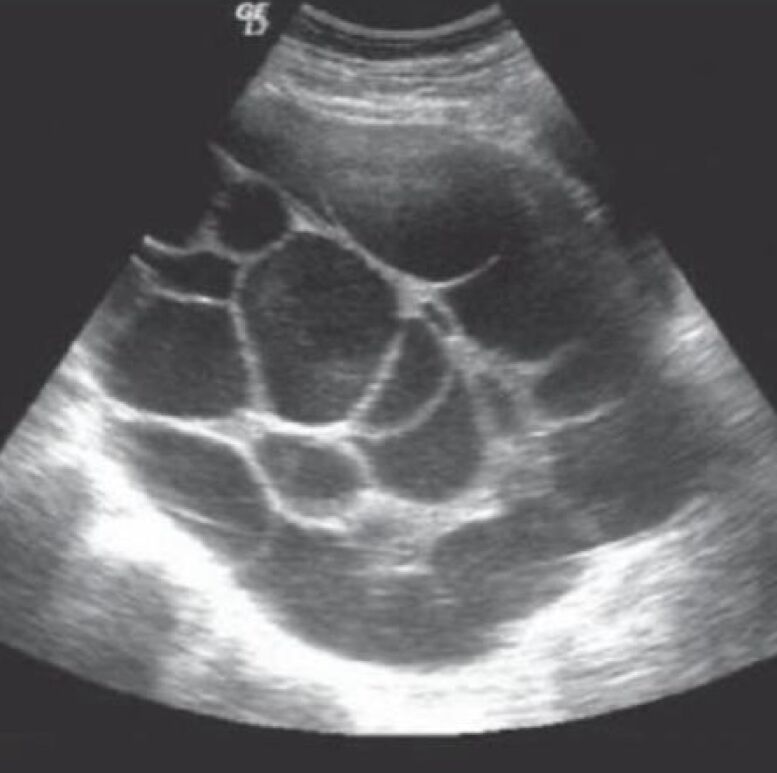

Polycystic ovarian syndrome(多囊性卵巢種):目前機制不清楚,目前認為是濾泡生長受干擾,多發生在第一次estrus cycle

臨床症狀:estrus cycle不規則,分為:

- 過多estrogen➡️慕雄狂:小且多的濾泡造成estrogen堆積。

- 過多androgen➡️雄性化:濾泡無正常功能,缺乏estrogen,造成androgen相對太多